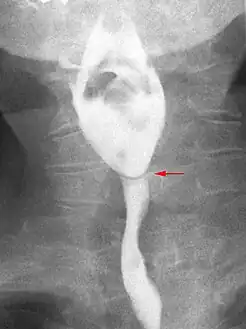

Web with "jet-phenomenon". Arrowhead on incomplete opening of the upper esophageal sphincter.

Esophageal web stenosis in barium swallow examination frontal view.